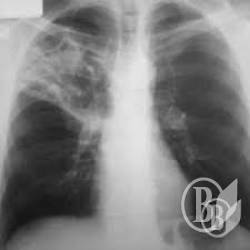

Анализ объявлений в «Вестнике государственных закупок» показал, что за прошлый 2014 год Черниговский противотуберкулезный диспансер шесть раз объявлял тендеры, пытаясь приобрести лекарства, дезинфекцийни средства, предметы одежды и аксессуары одежды из вулканизованной резины (перчатки латексные, нарукавники, передник защитный) рентгенопленку, флюропленку и химические реактивы.